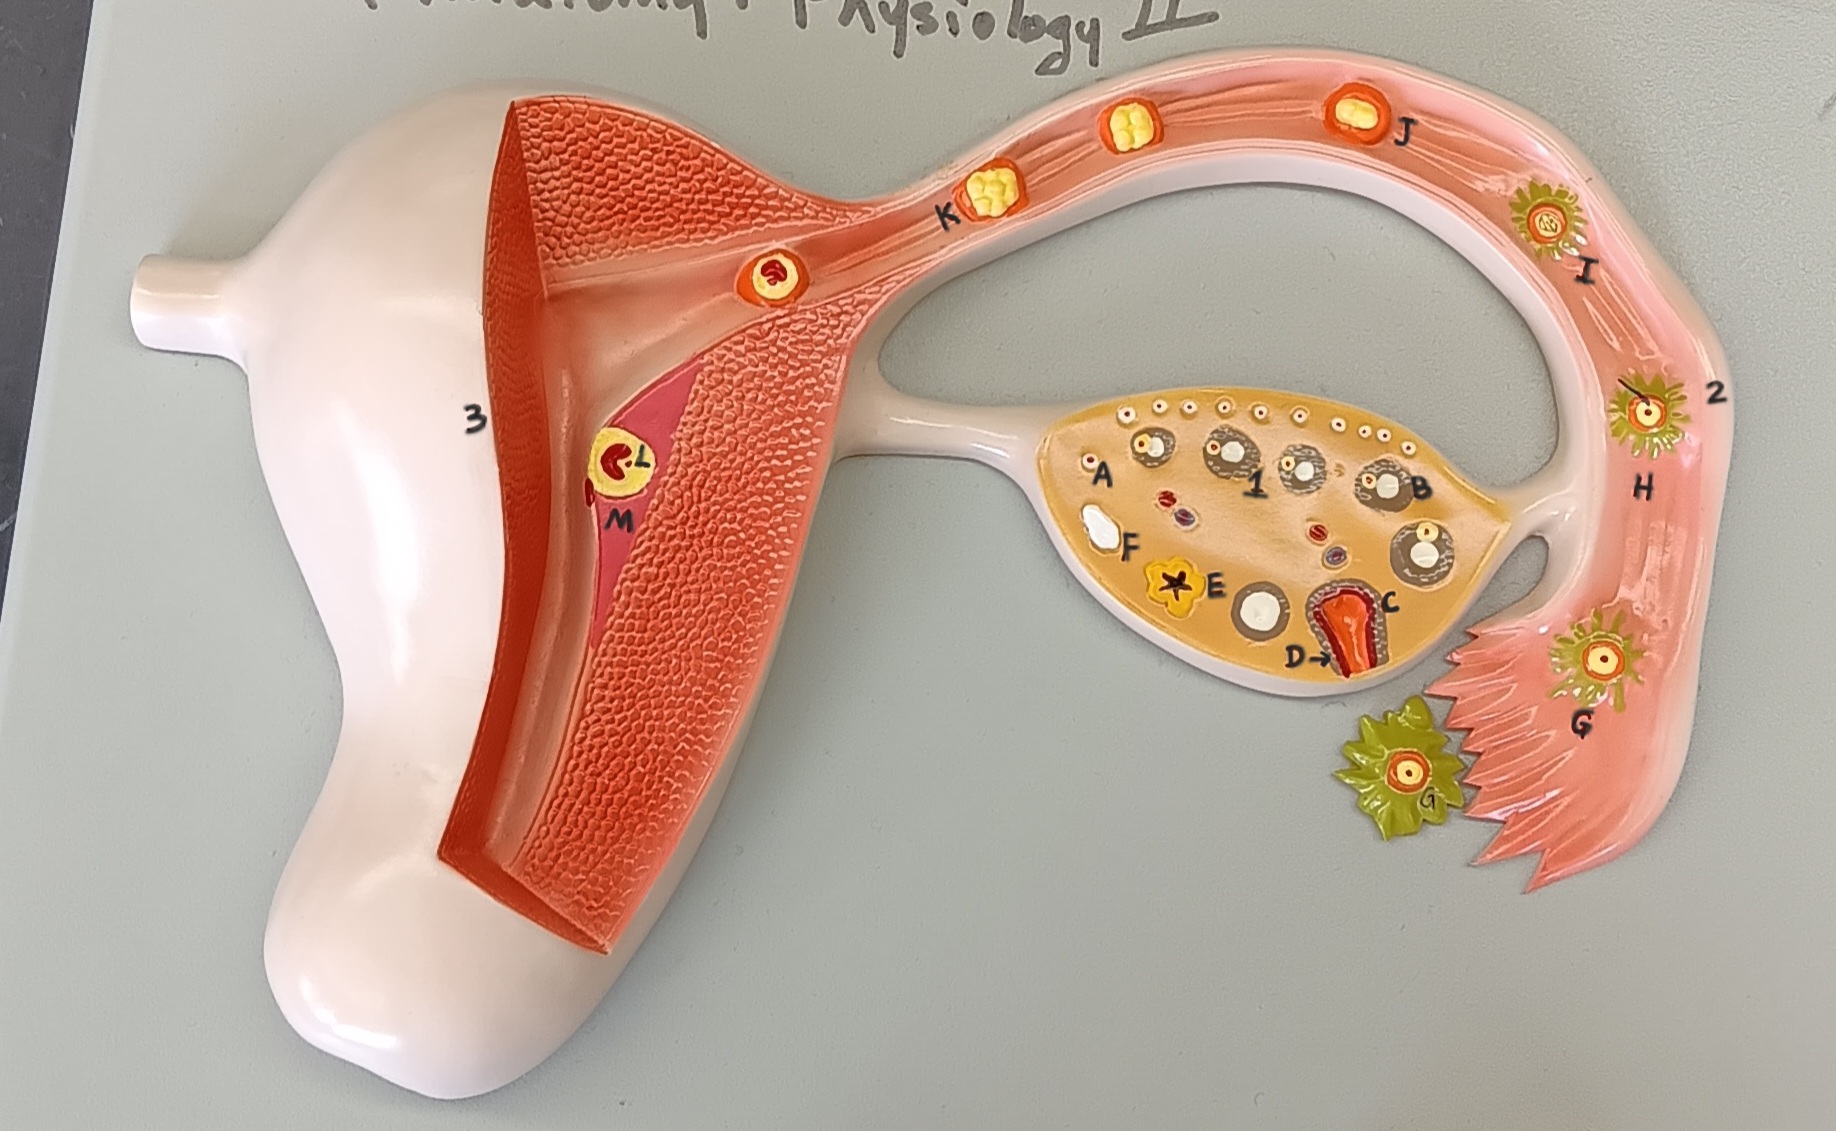

ovary

1

primordial follicle

a

secondary follicle

b

ruptured follicle

c

granulosa cells

d

corpus luteum

e

secondary oocyte

g

ovum

h

zygote

i

blastocyst

l

endometrium

m

corpus albicans

f

uterus

3

fallopian tube

2